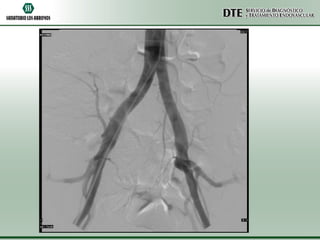

Angio TAC Aorta

abdominal y torácica

• Aorta torácica de diámetros conservados, en sus distintos trayectos.

•La emergencia de los vasos supraaórticos es de configuración y calibre conservado.

•Aorta abdominal de diámetros conservados, solo muestra placas de ateroma a nivel

infrarenal, sobre el sector latero-posterior izquierdo.

•Se menciona el nacimiento común de la arteria del T celíaco y la A mesentérica

superior.

•Las arterias renales muestran diámetros conservados.

•Las iliacas primitivas, internas y externas son de calibre conservado.

•Alteración de la morfología de múltiples arcos costales izquierdos. A cotejar con

antecedentes traumáticos.

•Quiste simple en el domo hepático.

•Resto sin particularidades.

Angio TAC Aorta •Aorta torácica de diámetros conservados, en sus distintos trayectos. •La emergencia de los vasos supraaórticos es de configuración y calibre conservado. •Aorta abdominal de diámetros conservados, solo muestra placas de ateroma a nivel infrarenal, sobre el sector latero-posterior izquierdo. •Se menciona el nacimiento común de la arteria del T celíaco y la A mesentérica superior. •Las arterias renales muestran diámetros conservados. •Las iliacas primitivas, internas y externas son de calibre conservado. •Alteración de la morfología de múltiples arcos costales izquierdos. A cotejar con antecedentes traumáticos. •Quiste simple en el domo hepático. •Resto sin particularidades.